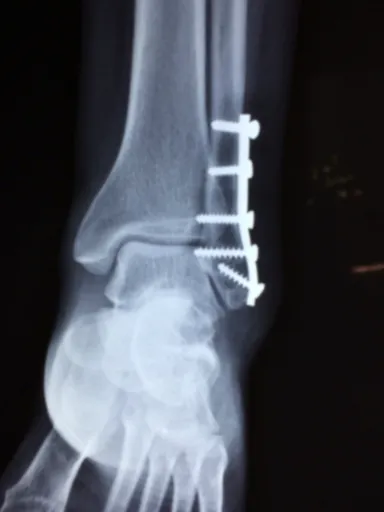

영상 진단검사

이후, 진단의 정확성을 높이기 위해 영상 진단검사가 필요할 수 있습니다. 이때 사용하는 대표적인 검사로는 X-ray, MRI(자기공명영상), CT(컴퓨터 단층촬영) 등이 있습니다. X-ray는 뼈의 구조를 확인하는 데 유용하고, MRI는 연조직, 예를 들어 인대나 연골의 손상을 평가하는 데 탁월하죠. CT는 좀 더 상세한 이미지를 제공하여 병변의 위치를 정확히 파악하는 데 도움을 줍니다.

MRI의 중요성

가장 흔히 사용되는 검사인 MRI의 경우, 고해상도의 이미지를 제공하여 대퇴부 통증의 다양한 원인을 탐지할 수 있습니다. 예를 들어, 연골 파열, 인대 염좌, 또는 관절염과 같은 문제가 있을 때 MRI는 그 결과를 명확하게 보여준답니다.